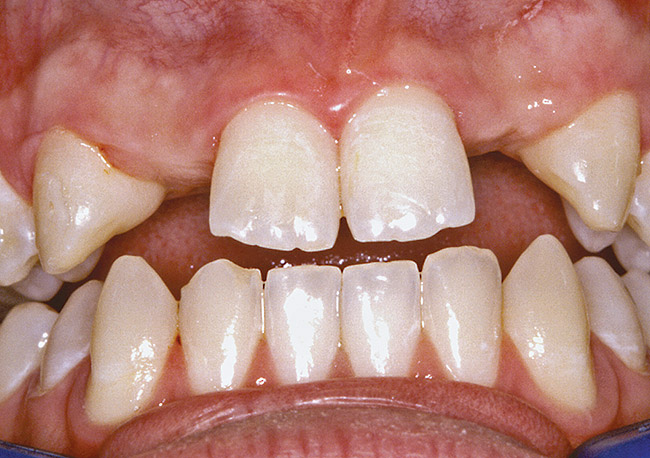

Figure 3  DIAGNOSTIC INFORMATION A difference in clinical appearance of the left lateral, buccal view.

Figure 3

Figure 4  DIAGNOSTIC INFORMATION Significant crestal width of keratinized tissue, buccal view.

Figure 4

Figure 26  VIRTUAL PLANNING AND SURGERY Before implant surgery, the orthodontic brackets were removed, revealing the position of the centrals, and the anatomical variations of the crestal tissue and lack of interdental papilla.

Figure 26

Figure 27   VIRTUAL PLANNING AND SURGERY Before implant surgery, the orthodontic brackets were removed, revealing the position of the centrals, and the anatomical variations of the crestal tissue and lack of interdental papilla.

Figure 27

Figure 28   VIRTUAL PLANNING AND SURGERY Before implant surgery, the orthodontic brackets were removed, revealing the position of the centrals, and the anatomical variations of the crestal tissue and lack of interdental papilla.

Figure 28